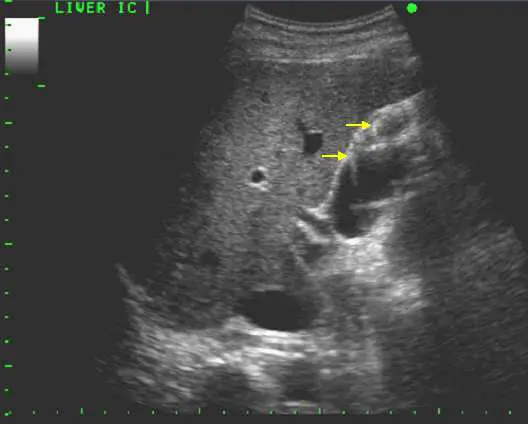

下圖為一體檢無症狀病人之腹部超音波圖,箭號所指最可能病灶位置為何?

本圖左上角標示「LIVER IC」,顯示掃描區域為肝臟(liver)肋間切面(intercostal view)。影像中可見:

- 肝臟實質(liver parenchyma):佔據影像上半大部分,呈現均勻中等回音(isoechoic)的細顆粒紋路。

- 兩個黃色箭頭所指結構:位於肝實質內偏右下方,可見一個無回音(anechoic,完全黑色)、壁薄且光滑的囊袋狀結構,輪廓清晰。此即膽囊(gallbladder)的典型超音波表現:

- 形態:梨形(pear-shaped)

- 回音特性:無回音(anechoic)—膽汁為液體,超音波幾乎不被吸收

- 管壁:薄壁(正常 < 3 mm),回音稍高(echogenic wall)

- 後方回音增強(posterior acoustic enhancement):液態結構後方組織顯示回音增強

- 影像下方可見管狀低回音結構,為鄰近血管(portal vein 或肝靜脈)的斷面。

膽囊位於肝臟臟面的「膽囊窩(gallbladder fossa)」,即肝右葉與方葉(quadrate lobe)之間,緊貼肝下緣。因此在